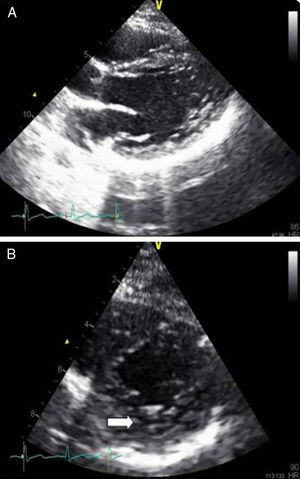

Monitorizada em ambiente de unidade de cuidados intensivos cardíacos, realizou ecocardiograma, que revelou ventrículo esquerdo de dimensões normais com fracção de ejecção do ventrículo esquerdo (FEVE) global ligeiramente deprimida (FEVE ± 45%) e imagens compatíveis com VENC a nível apical (trabeculações exuberantes com relação camada trabeculada/não trabeculada superior a dois e com fluxo detetado por Doppler de cor ao nível das mesmas) (Figuras 4 e 5). Foi efetuada coronariografia, revelando ausência de doença coronária.

A paciente teve alta clinicamente estável. Atualmente, encontra-se bem, sem sinais clínicos de ICC. Encontra-se dependente da função pacing do CDI de dupla câmara, sem choques detetados. O rastreio de familiares diretos revelou ECG normais, com os ecocardiogramas dos seus filhos a revelarem imagens sugestivas de não compactação miocárdica inferior e lateral (Figura 6) (com o ECG de alta resolução dos mesmos a não revelar alterações). Aguarda-se atualmente o estudo genético da paciente.